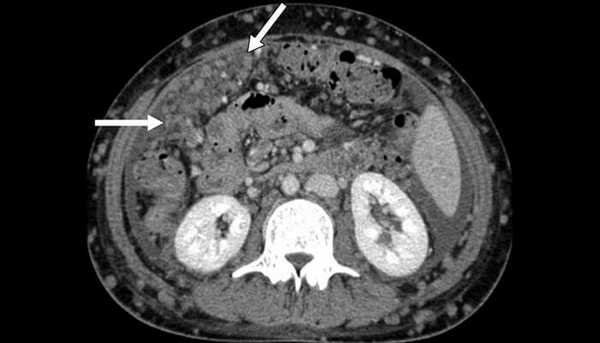

Канцероматоз брюшины, компьютерная томография

Нередко прогрессирующее опухолевое поражение брюшины так и остается бессимптомным, на первый план выходят признаки накопления внутрибрюшной жидкости и вызываемые асцитом симптомы сердечно-легочной недостаточности: одышка, отеки нижней половины тела, застой в легких, кашель, нарушение сердечной деятельности, слабость. Болевой синдром, как правило, очень слабый.